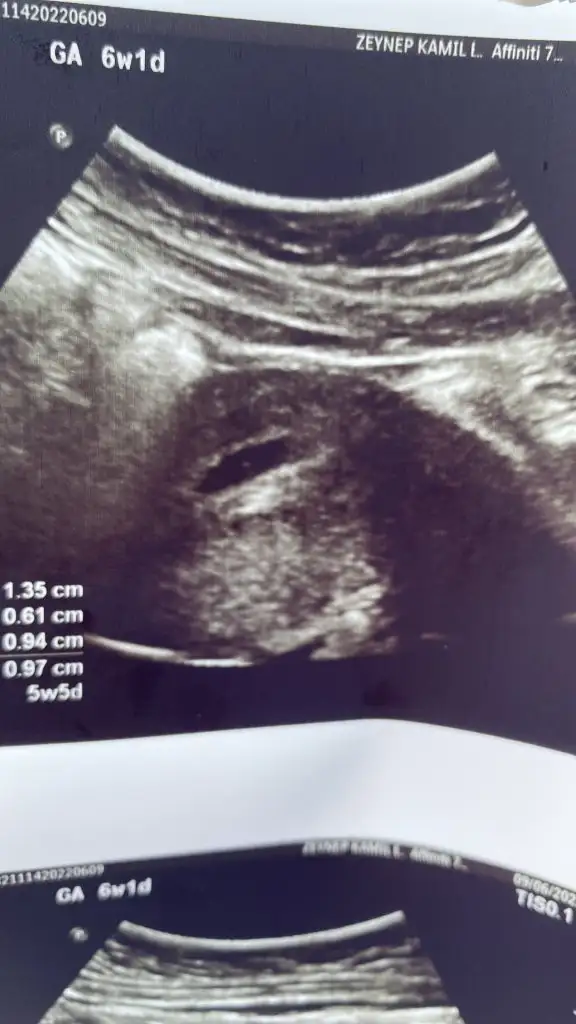

Merhaba cnm Benimkini de bakarmisin 6+3 vajinal ultrason